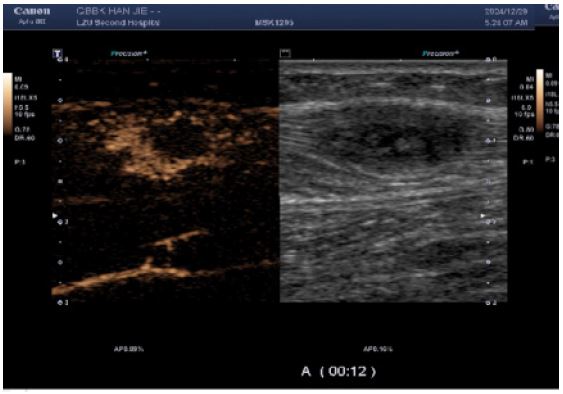

CEUS (performed next day): Subsequent CEUS performed 24 hours post-initial scan demonstrated heterogeneous enhancement at 25 seconds post-contrast injection, characterized by peripheral hyper-enhancement and a large central non-enhancing area – an imaging pattern misinterpreted as indicative of a benign lesion.

The reasons for the misdiagnosis of this patient as a benign tumor were as follows: (1) The initial diagnostic context involved routine ultrasound without documented extramuscular malignancy, precluding sufficient justification for metastatic suspicion; (2) Sonomorphological mimicry manifested as well-circumscribed, spindle-shaped anechoic foci with smooth margins, distinct hyperechoic capsules, and posterior acoustic enhancement within the calf musculature—features pathognomonic for schwannoma yet discordant with the infiltrative borders characteristic of aggressive malignancies; (3) Vascular analysis (Figure B) revealed sparse punctate vascular signals rather than the abundant internal/peripheral flow or large perforating vessels typical of subcutaneous cancers; (4) CEUS kinetics further reinforced misdiagnosis through arterial-phase peripheral hyper-enhancement with central non-enhancing zones, maintained circumscribed margins, and early washout in adjacent tissues—collectively aligning with classical benign enhancement profiles and creating a compelling illusion of non-malignant pathology.